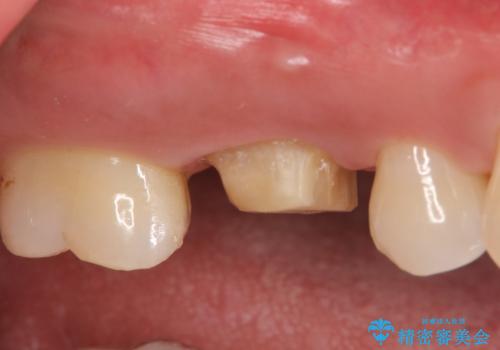

- 見た目が気になるため右上6のゴールドクラウンをセラミックにしたいといらっしゃった方の症例です。

再根管治療を御希望されたため根管治療を行った後、メタルボンドクラウンによる補綴を行いました。